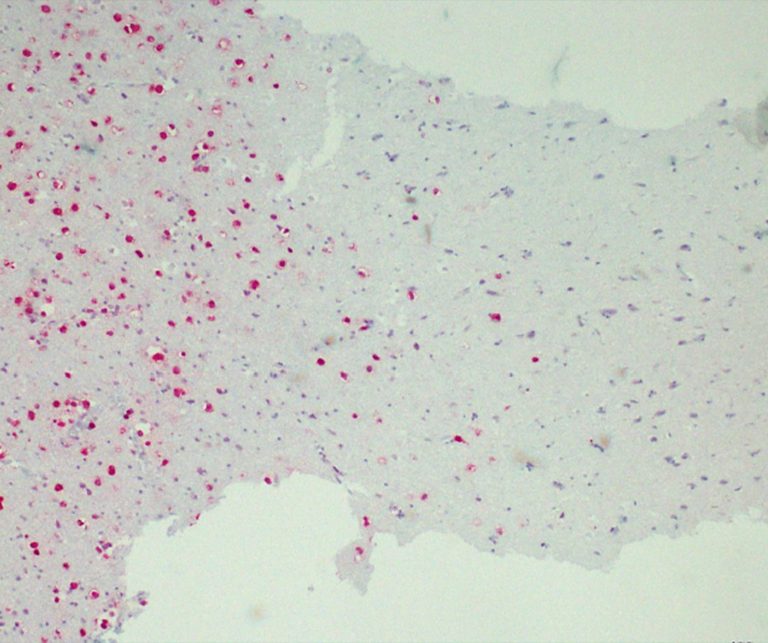

Infection Markers